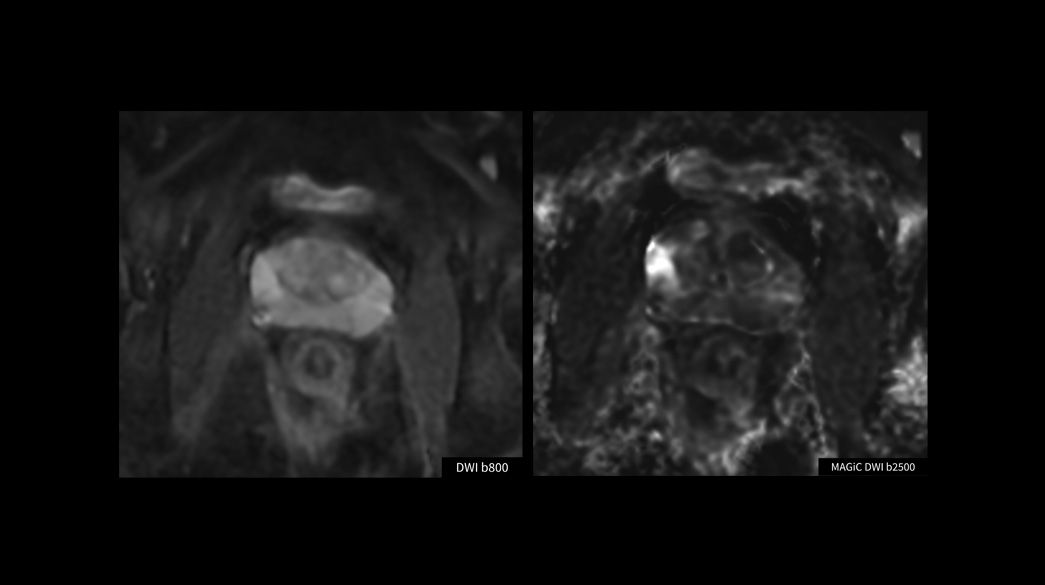

Advanced-DWI1040-x-585

Read case study ico-caret-right